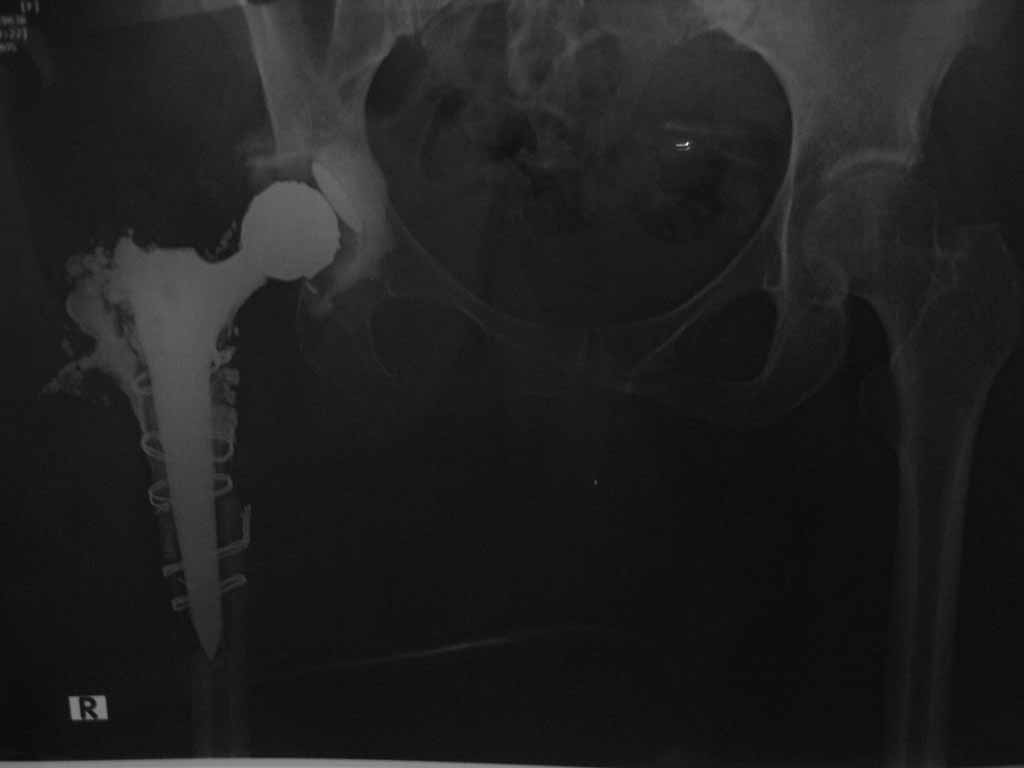

В августе 2010 года оперирована по поводу коксартроза пр ТБС Тотольное эндопротезирование. Видемо, во время обработки бедренного канала треснула вся проксимальная часть бедра. В послеоперационном периоде опер.рана не заживала..открылся свиш. нагноение!!! К нам поступила 30.05.2011 г . В настоящая время серозо-гнойное отделяемое из раны.

Оперирована.2.06.2011г. Удален эндопротез, серкляжи и несколько секвесторы (проксимальный конец бедра). Образовался большой дефект. Дефект заполнен цементным спейсером. Активный дренаж.В дальнейшем